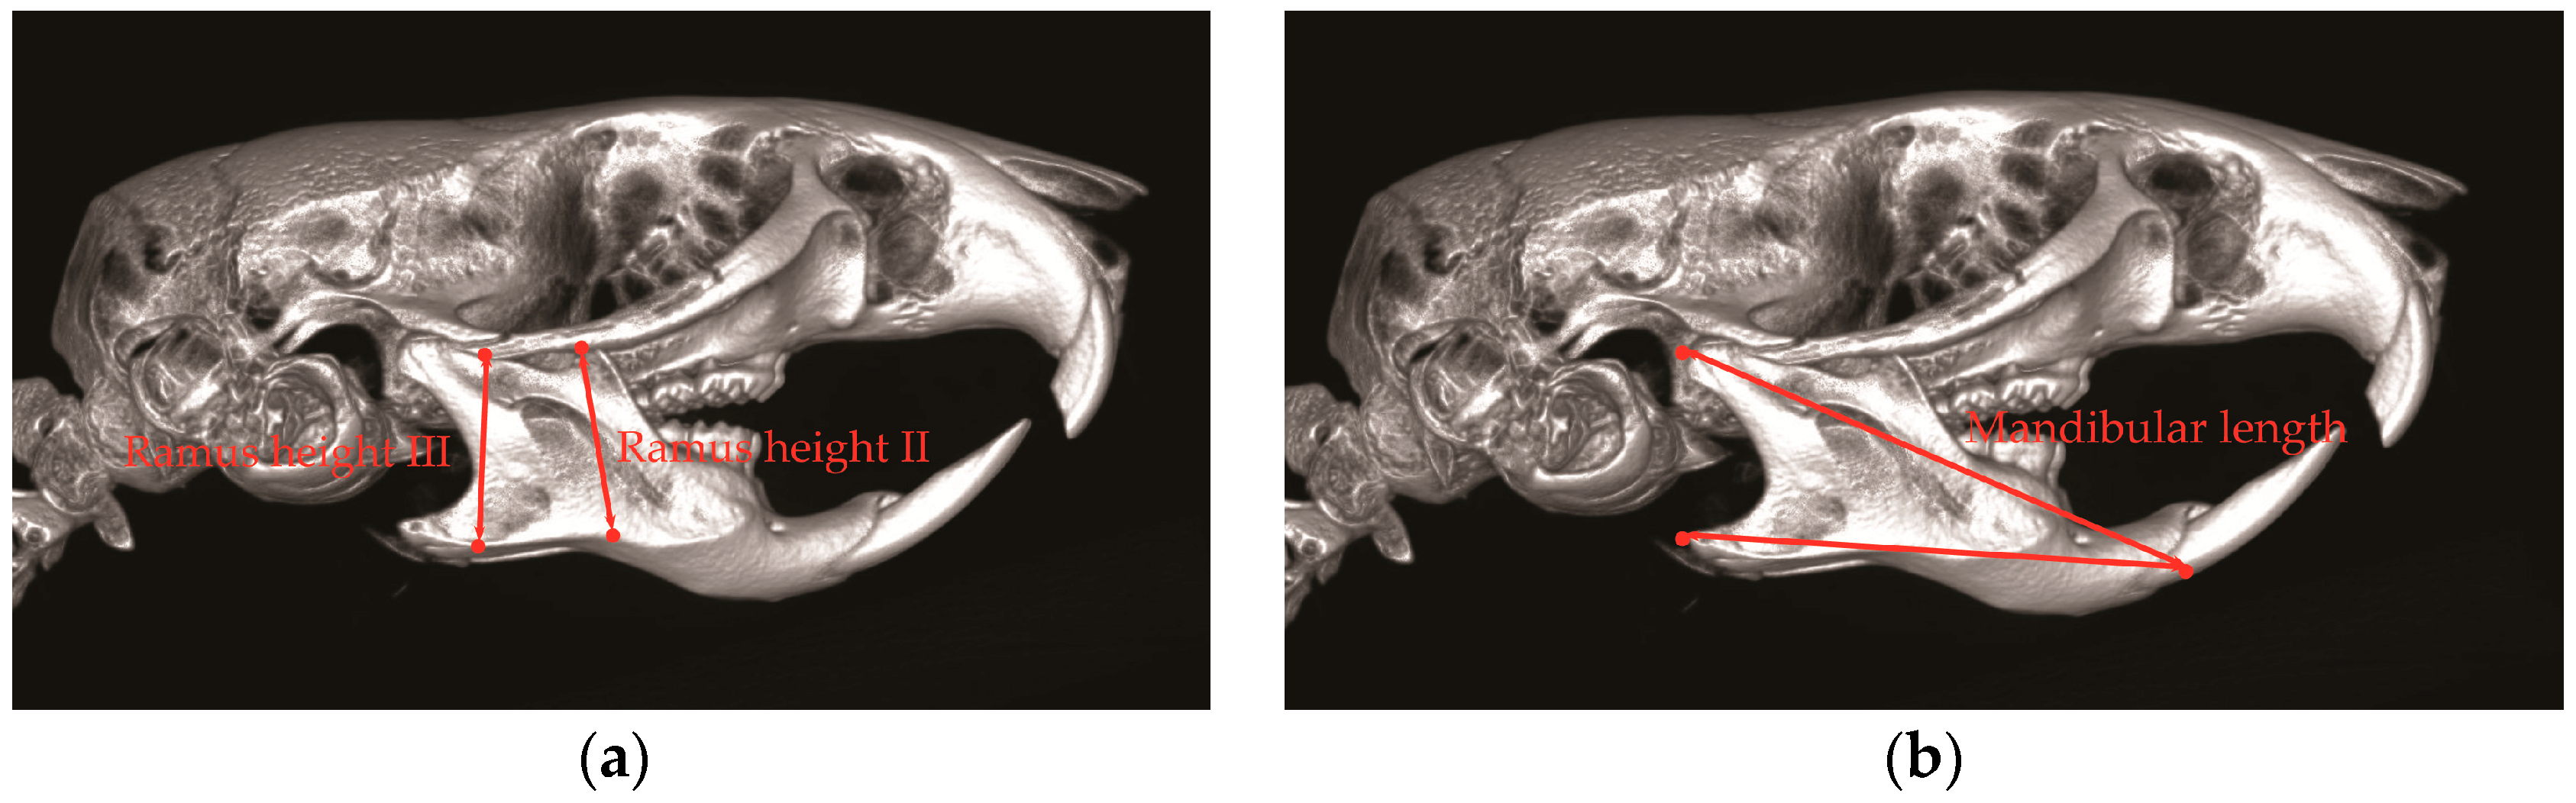

BTX injection in masseter muscles decreases muscle activity and affects the maxillofacial bone growth in animal studies [16,45]. Masseter muscle is attached to the zygomatic arch and inserted to the ramus and angle of mandible [47]. With the use of unilateral BTX injection in rabbit masseter muscle, the bone volumes of zygomatic and mandibular bone are significantly reduced [43]. In addition, with BTX injection in the masseter of growing rat, the mandibular length and ramus height are also significantly reduced (Figure 1 and Figure 2) [17]. The unilateral injection of BTX in masseter muscle induces the growth retardation of mandible (Figure 2) [17,18,48] and causes mandible deviation and facial asymmetry in adult rats (Figure 2c,d) [36]. The BTX injection in temporalis muscle also affects craniofacial bone growth. The temporalis muscle extends from the temporal bone and to the coronoid process of mandible [18]. Rats that received BTX in unilateral temporalis muscles had a significantly reduced skull base dimension [18], and the premaxilla, maxilla, and zygomatic arch dimensions were also decreased [18]. These previous animal studies show that the hypofunction of masticatory muscle by BTX injection affects the growth potential of the involved craniofacial bone and induces morphological changes in facial bone growth [17,43].

Figure 1.

Anthropometric measurement of ramus height and mandible length. (a) Ramus height II is the distance between the zygomatic arch and inferior point of antegonial notch; ramus height III is the distance between the temporozygomatic suture of zygomatic arch and inferior point of mandible; (b) Mandible length is the distance between posterior point of mandible condyle and anterior point of mandible crest in mandible incisor.